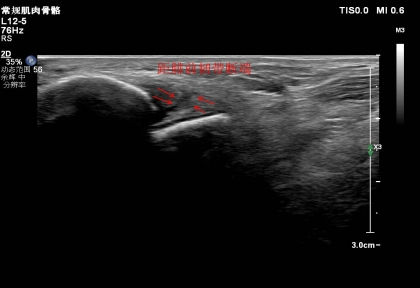

3. 距腓前韌帶斷裂